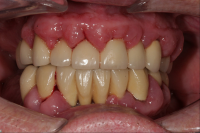

Gingivit är tandköttsinflammation som visar sig genom marginal blödning vid sondering, men där tanden ej har någon förlust av käkbensfäste.

Diagnosen gingivit används vid tänder med marginal inflammation och blödande tandkött, men ingen förekomst av marginal benförlust. Fickdjup 1–3 mm, pseudofickor kan förekomma upp till 5 mm.

Ödematös, rodnad och blödande gingiva.